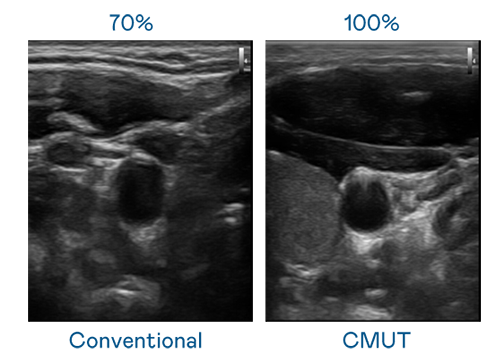

CMUT 技术是一种用电容式微机电元件来产生超音波讯号的技术。与传统 PZT 压电式技术相比,CMUT 频宽增加 30%,更宽频的超音波讯号让影像解析度大幅提升,是实现高影像品质医疗超音波扫描、促进精准医疗发展的关键技术。

超音波影像的解析度高低,首先取决于探头能发出的讯号频宽。问鼎 CMUT 可提供高清晰的超音波讯号,提供高频宽、高灵敏度、影像纹理细节更高的超音波影像,协助医护人员缩短影像判读时间及利用精准的医疗影像进行诊断。